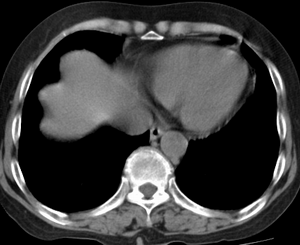

以下是引用齐原在2006-11-8 23:21:00的发言:[br]肝脏体积增大.肝表凸凹不平,肝内胆管扩张,胆总管扩张,胆总管末端突然截断,胰腺勾突增大,形态不规则.胰管扩张.考虑胰头癌.并低位梗阻性胆系扩张,胆囊炎.脾大.建议增强

以下是引用dyqct在2006-11-9 9:14:00的发言:[br]肝大,表面呈波浪状,肝内外胆管扩张,胆总管下端腔内见小结节状等密度影,胰管轻度扩张。胆囊显示不清。[br]考虑:1、胆总管下端占位性病变(等密度结石?壶腹部肿瘤?);[br] 2、肝硬化?[br] 3、建议增强扫描进一步检查。